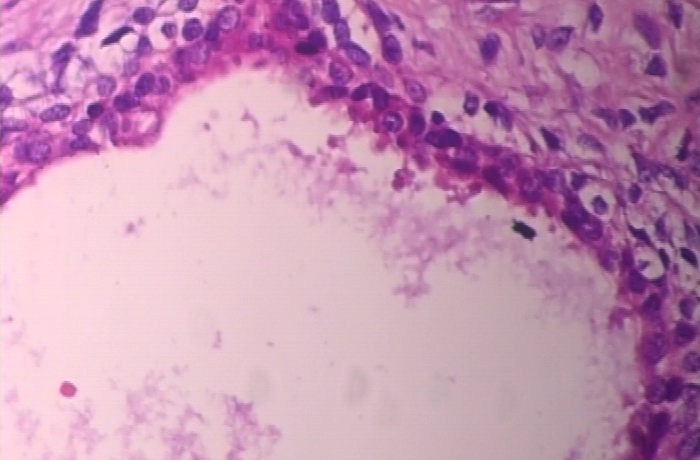

Contains the LR, HR and Fine-tuned Images with evaluation scores i.e MSE and PSNR values.